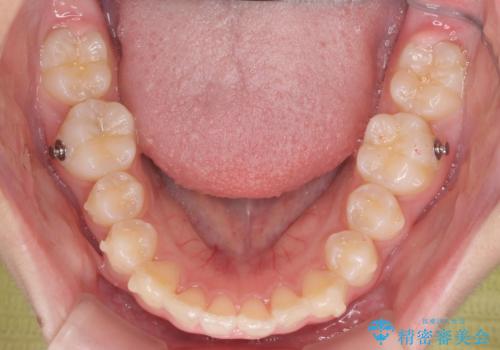

子供の出っ歯 生え代わりと成長期を利用して非抜歯で矯正

- 出っ歯を主訴に来院。

生え代わりを待ってから矯正を始めました。

特に右側のかみ合わせがずれていたため、上の奥歯を後ろに下げています。

下顎も前方に成長し、前歯のかみ合わせも同時に深かったのを浅くすることができました。